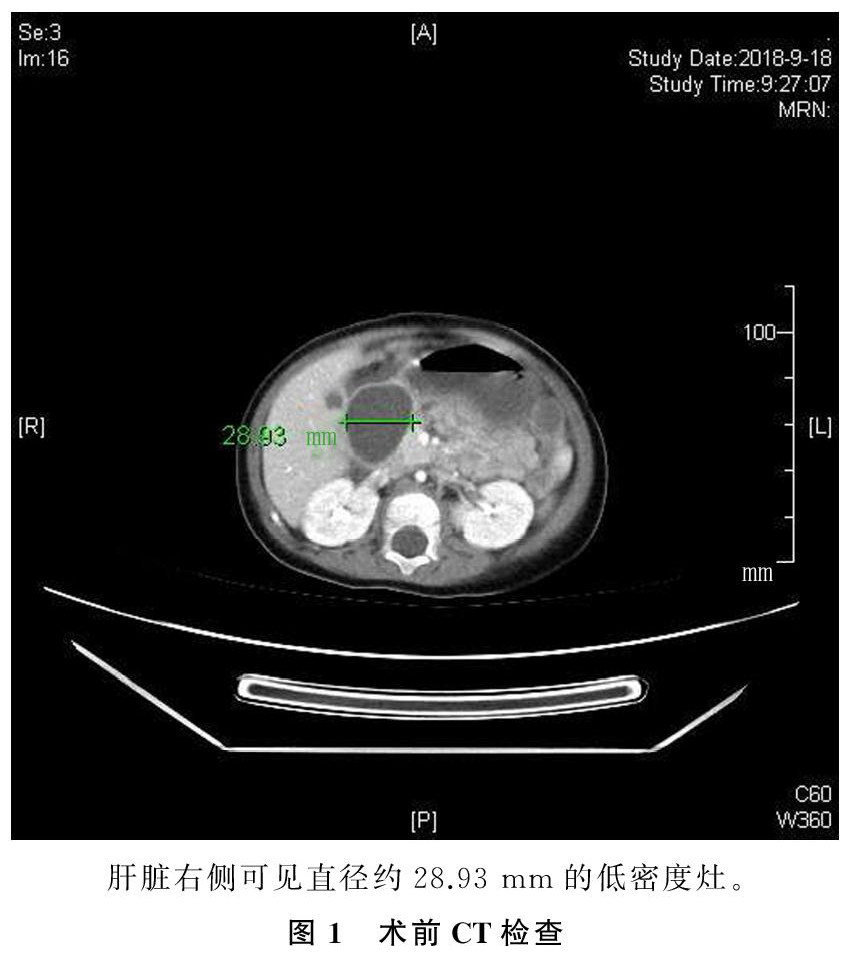

[摘要] 目的 探讨误食“海洋宝宝”的临床特点,提高对儿童误食异物的认知。方法 回顾性分析我院确诊的1例误食“海洋宝宝”病儿的临床表现、治疗过程和转归。结果 通过手术切开空肠将异物取出,行肠切开吻合术。术后1周痊愈出院。结论 误食“海洋宝宝”导致的肠梗阻病史不明确,易延误治疗,临床应该提高警惕,早发现、早治疗。(剩余2846字)